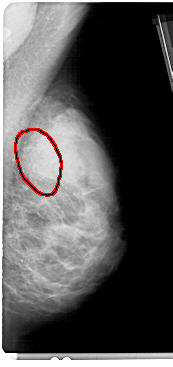

A_1364_1.LEFT_CC

LEFT_CC LINES 4756 PIXELS_PER_LINE 2386 BITS_PER_PIXEL 12 RESOLUTION 43.5 NON_OVERLAY

FILE: A_1364_1.RIGHT_CC.OVERLAY

TOTAL_ABNORMALITIES 1

ABNORMALITY 1

LESION_TYPE CALCIFICATION TYPE AMORPHOUS DISTRIBUTION SEGMENTAL

ASSESSMENT 4

SUBTLETY 3

PATHOLOGY BENIGN

TOTAL_OUTLINES 1

BOUNDARY